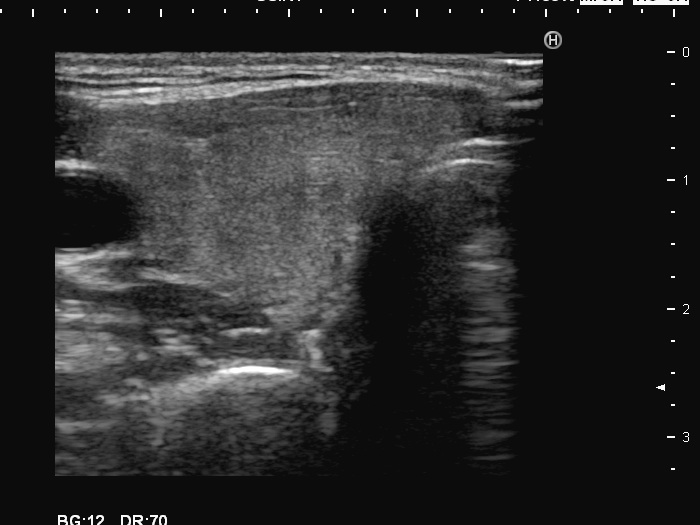

Left lobe, longitudinal scan

This is the usual course of Graves' disease regarding the change in echo pattern - before, during and after the activity of the autoimmune process. The only exception is the change in the size of the thyroid. In most cases, the thyroid increases during the activity of the disease, then returns to normal. However, in this patient the age counts: at the first examination, the patient was only 15-year-old.

- There are two situations in Graves 'disease where circulation is increased. At the stage of disease activity and when hypothyroidism is observed with medication. In the former case, the blood flow is almost always increased, in the latter it can be decreased and increased.